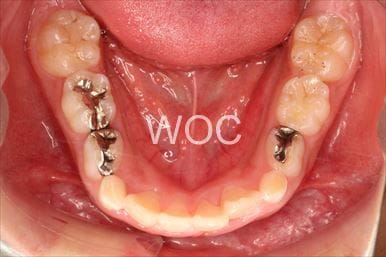

叢生

治療前1

治療前2

治療前3

治療前4

治療前5

- 年齢:8歳2ヶ月

- 主訴:ガタガタ

- 診断名:叢生、上顎前突、過蓋咬合

- 装置:機能的矯正装置

- 期間:6年5ヶ月 ※

- 費用:基本矯正料金:350,000円